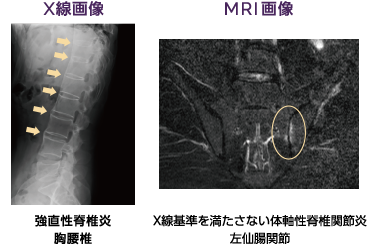

画像検査

X線検査やMRI検査で背骨、骨盤の状態を観察します。初期段階の骨の変化をみつけるにはMRI検査が役立ちます。

画像提供:辻 成佳 先生